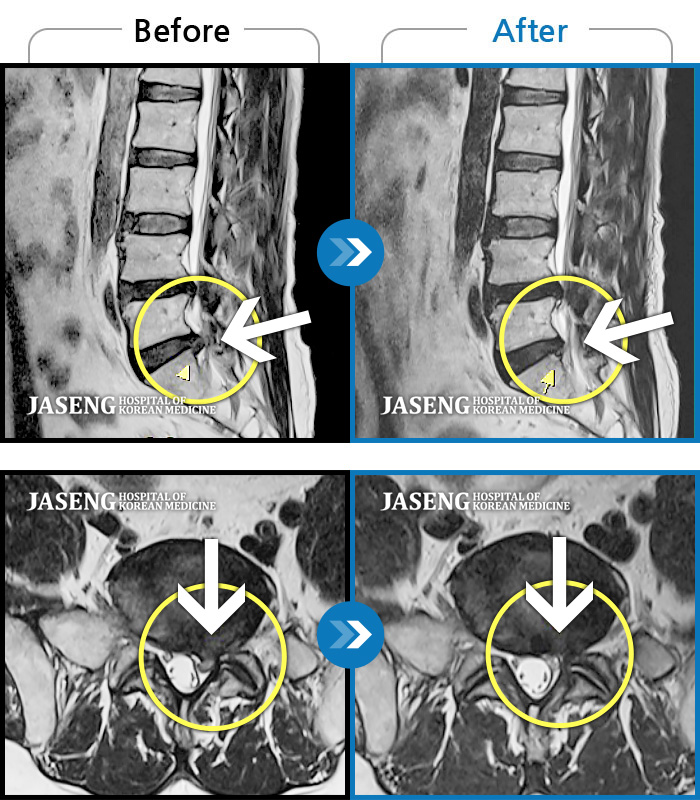

허리디스크

광주 · 장영우 원장

허리 우측 골반 통증, 우측 다리 저리고 엄지발가락 마비 증상

촬영시기

2019.11.05 ~ 2020.05.23

2020.05.29

조회수 641